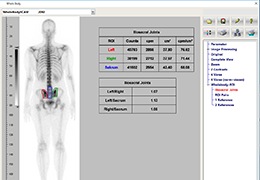

ANYTHINK 经导管主动脉瓣膜置换术分析系统